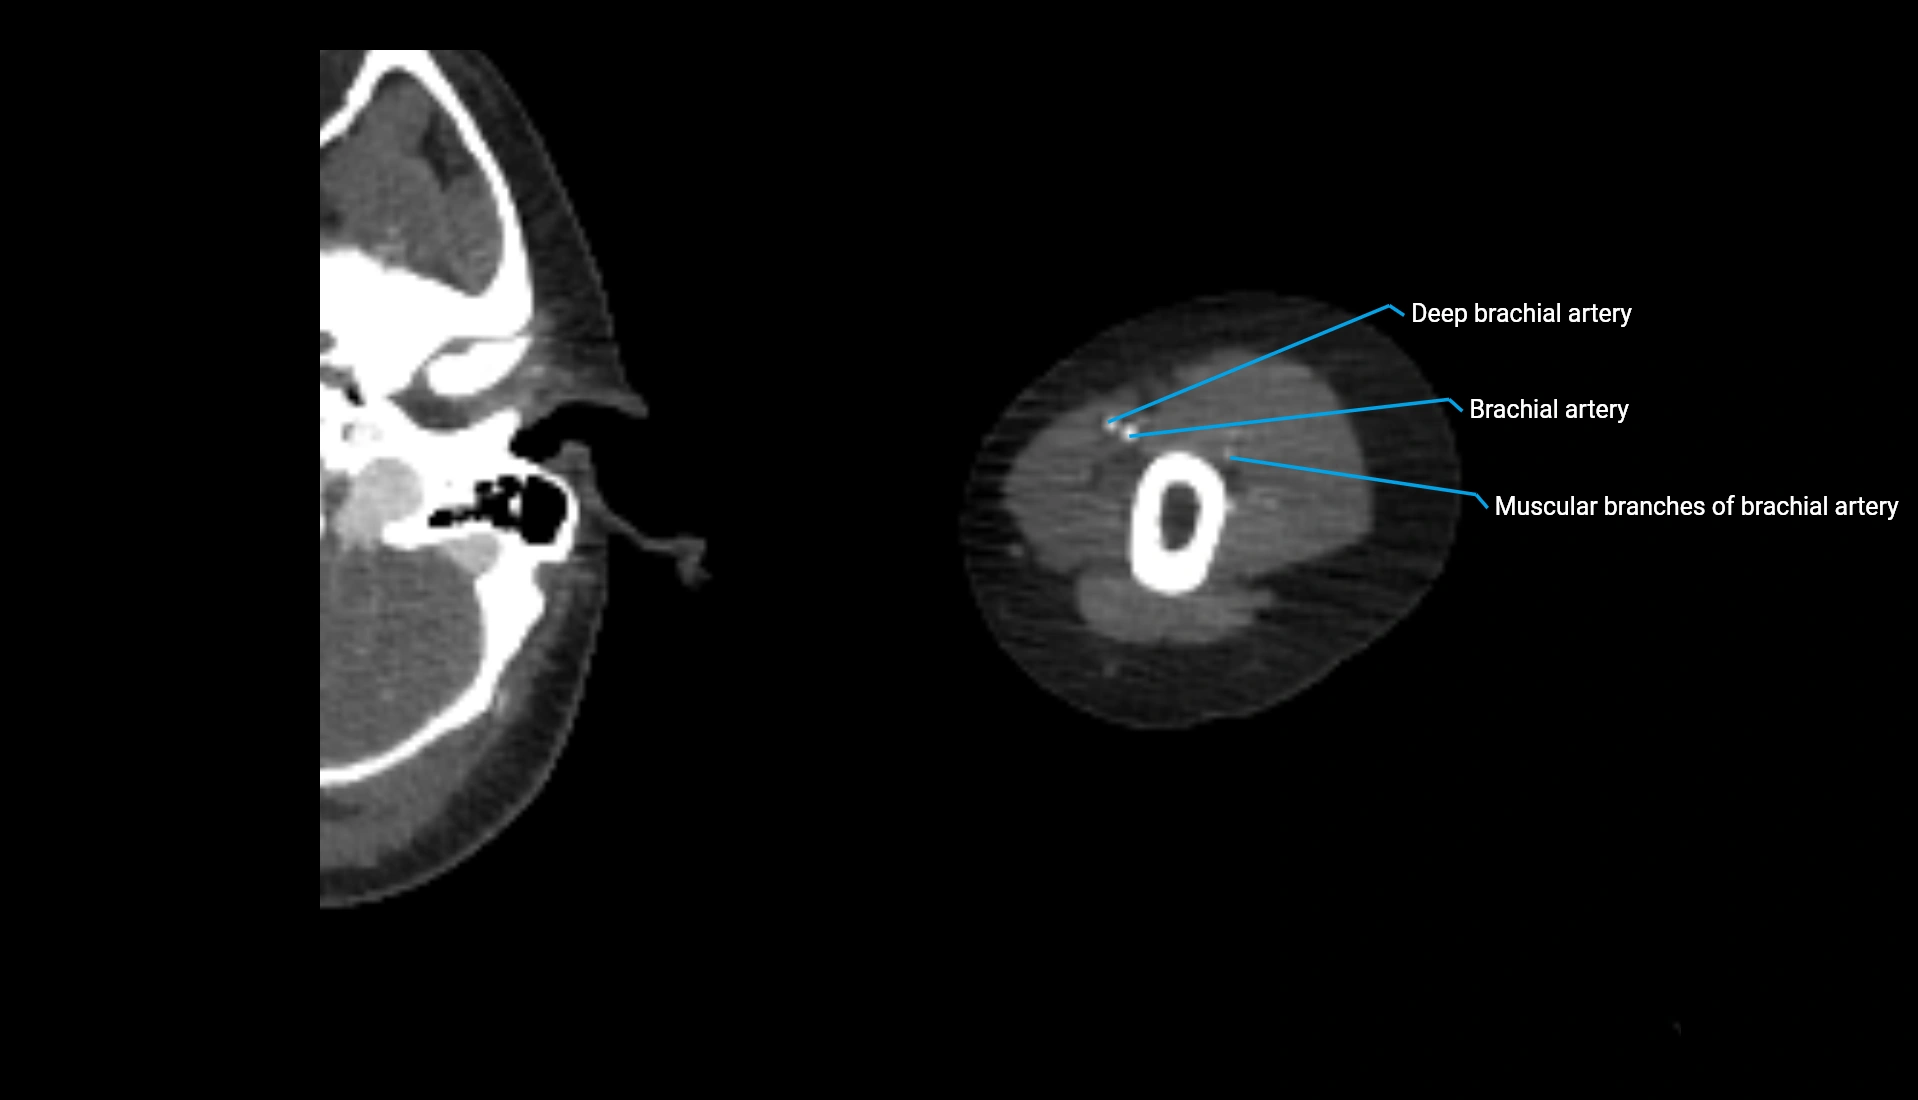

CT Appearance

Non-Contrast CT:

• Cortex: High-density, sharply defined

• Subchondral bone: Dense cancellous matrix

• Articular surface: Smooth concave contour articulating with the capitellum

• Excellent for evaluating bone integrity, alignment, and subtle fractures